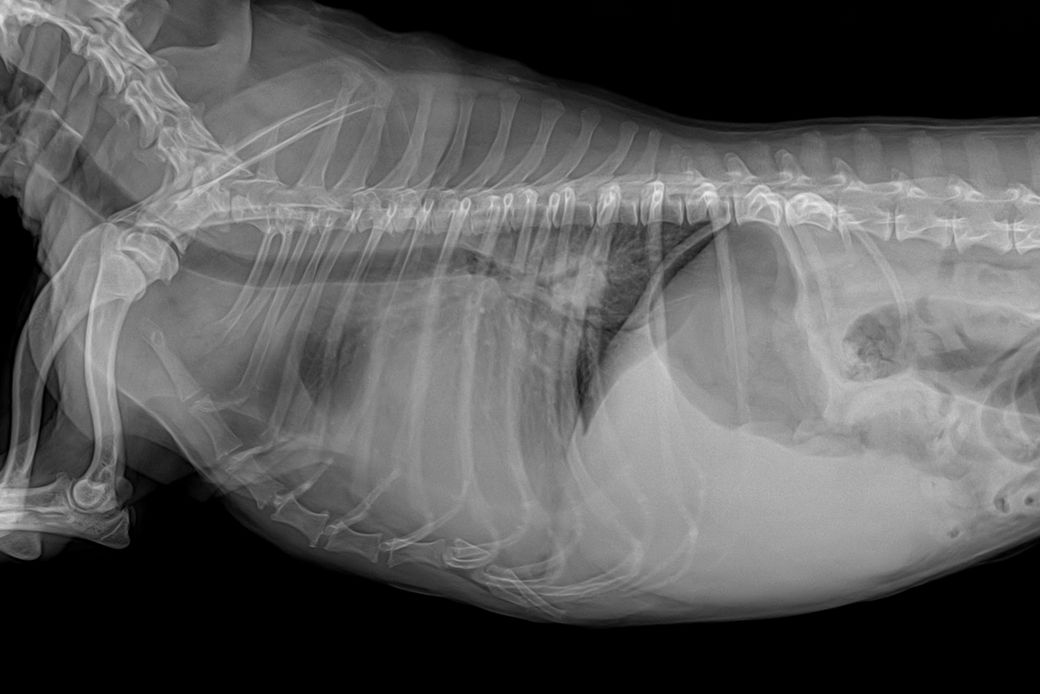

심장도 키기가 매우 크고, 좌심방 돌출이 있으며, 경미하지만 폐수종이 발생한 상태면서, 흉수도 보입니다.

또한 간의 크기가 큰데, 종괴 양상이 보여 간암 가능성이 매우 높아 보이니 복부 초음파 검사와 심장 초음파 검사 모두 필요합니다.